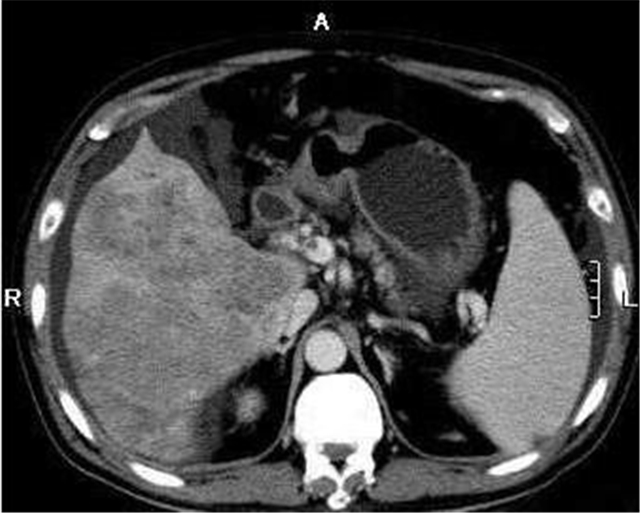

孙先生,34岁,主述近日来一直肝脏和肩胛骨部位钝痛,偶感恶心,食欲不振。我们经过肝脏核磁共振和甲胎蛋白等检查,基本 确诊为乙型肝细胞癌。

肝细胞肝癌(以下简称肝癌)是我国癌症的癌中之王。 肝癌(Liver cancer)是一种发生于肝脏的癌症。诱发肝癌的主要因素是病毒,我国全民要打的乙肝疫苗就是用来抗肝癌和预防肝癌。肝癌的主要发病就是由病毒引起炎症,进而引起肝炎,然后经过治疗,炎症再变成脓疱,脓疱然后结疤就形成了肝硬化,然后进一步形成了肝癌。